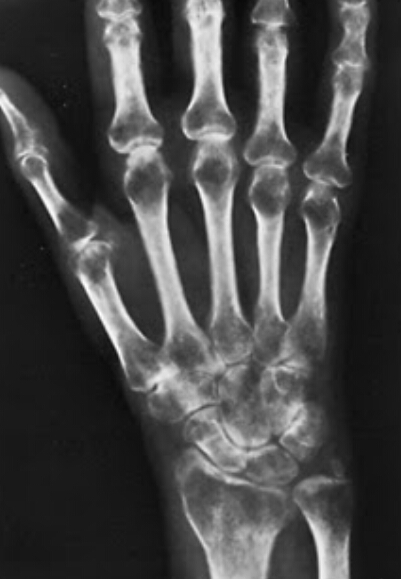

A person comes in with this xray. They have just gotten out of a cast. What is the diagnosis?

disuse osteoporosis